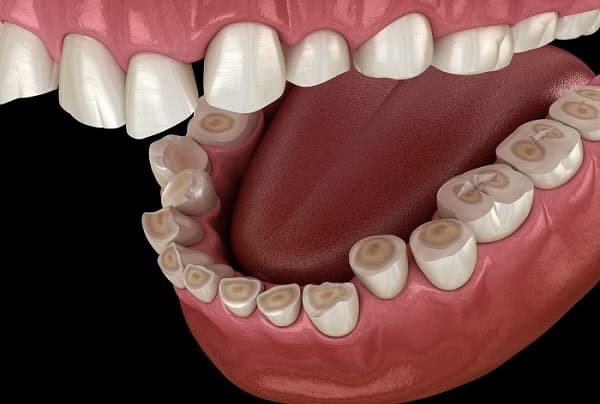

اگر با عمل ریفلاکس معده، اسید معده و محتویات داخل معده به دهان بازگردد، آسیب هایی جدی به دندان ها وارد می شود. همان طوری که می دانید اسید دشمن مینای دندان می باشد، با از بین رفتن مینای دندان شرایط برای پوسیدن دندان ها راحت تر می شود و دندان ها زودتر به پوسیدگی دچار می شوند. در پی پوسیدگی دندان ها، حساس شدن و ضعیف شدن آن ها را شاهد هستیم. کاهش یافتن بزاق دهان از دیگر عوامل ریفلاکس معده می باشد و نتیجه ی کاهش بزاق دهان نیز همکاری باکتری های داخل دهان با مواد و خوراکی های بین دندان هاست.

خوب است بدانید اگر باکتری های موجود در دهان به راحتی بتوانند با اضافه های غذا که در لا به لای دندان ها مانده است ارتباط بگیرند و مخلوط شوند، دندان ها به راحتی و سریع تر می پوسند و خراب می شوند. به همین خاطر است که به برخی افراد که دچار ریفلاکس معده می شوند، جویدن آدامس های بدون طعم توصیه می شود. خوب است بدانید جویدن آدامس باعث افزایش بزاق دهان می شود. در برخی موارد ریفلاکس معده بر ظاهر دندان ها از جمله رنگ آن ها تاثیر می گذارد. در مواردی که ریفلاکس شدید باشد و دائم مواد و محتویات به داخل دهان بازگردد ممکن است بیماری های لثه ای را برای فرد به وجود آورد.